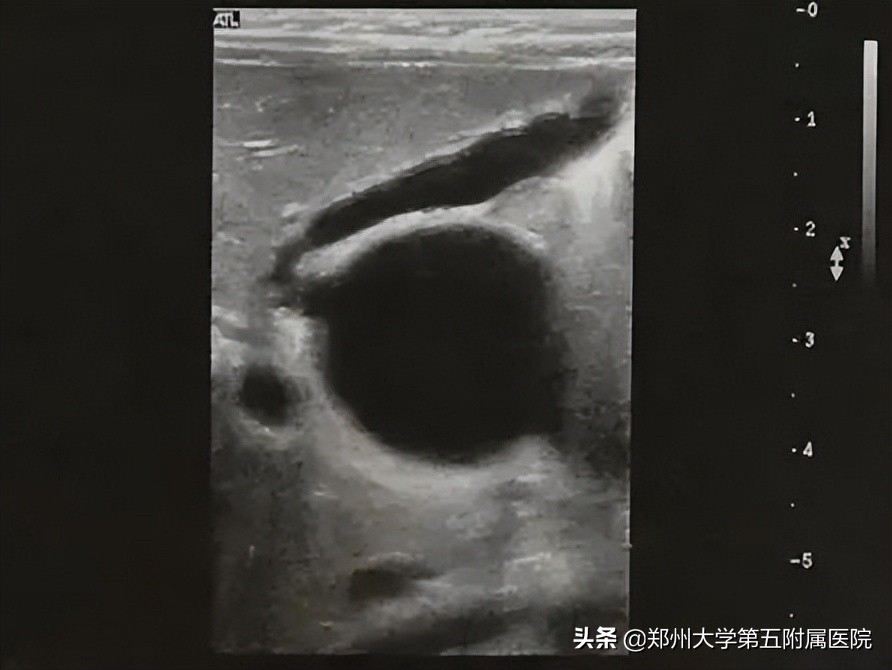

胆道闭锁 患儿生后即出现黄疸、进行性加重、皮肤巩膜黄染、面色暗黄、大便淡黄色或白色陶土样等症状。由于新生儿胆总管纤细难以观察,因此通过以下胆囊形态变化判断是否胆道梗阻: 胆囊大小正常但形态僵硬 (图2),边缘不光整,长度可达2-3cm,内径大于0.4cm,可有小的憩室样结构形成; 小胆囊 ,长度小于1-1.5cm,内径0.2cm,充盈差; 胆囊小而且无充盈,仅可见胆囊痕迹,喂奶后无变化 ;以上三种胆囊均可合并有 胆总管区囊肿,可与胆囊管及胆囊相通 ,但 与肝左、右管不相通 (见图3); 小部分病例 可见到 肝内胆管局限性扩张 (图4);病程后期(3个月以上),显示肝硬化改变(图5)。

▲ 图2